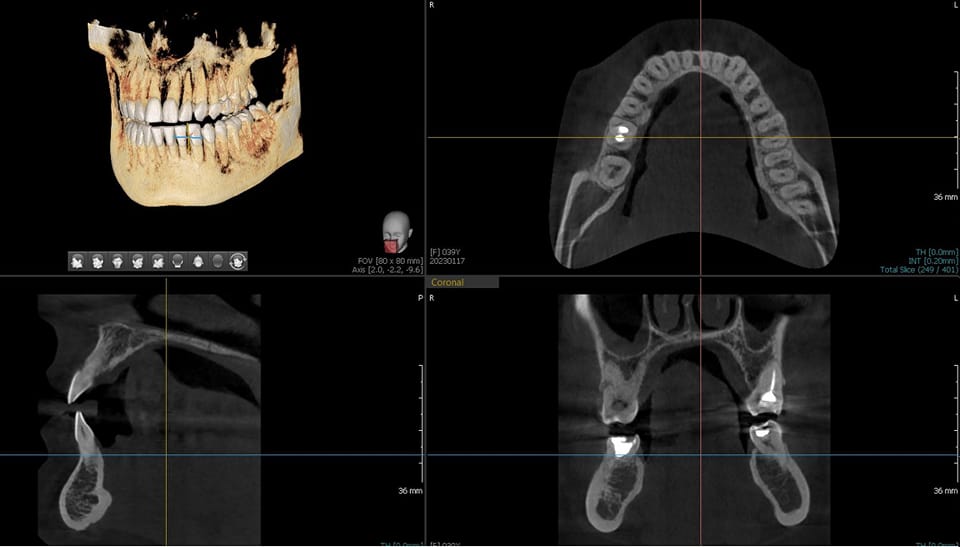

1. Tomografia komputerowa wiązki stożkowej (CBCT)-3D

Najbardziej zaawansowane i precyzyjne badanie radiologiczne znajdujace zastosowanie w implantologii (pozwala określić kształt, strukturę, grubość kości jak i jej gęstość oraz wykonanie odpowiednich pomiarów), w leczeniu kanałowym (umożliwia uwidocznienie dodatkowych kanałów oraz anomalii anatomicznych), w chirurgii stomatologiczne ( obrazowanie m.in. zmian patologicznych o typie guzów, torbieli, zmian kostnych).

Dzięki zastosowaniu w naszym tomografie szerokiego pola obrazowania, jesteśmy w stanie uzyskać obraz zarówno szczęki jak i żuchwy, a także całej zatoki szczękowej, w jednym badaniu co stanowi korzyść dla pacjenta w postaci tylko jednej ekspozycji, a dla nas możliwość dokładnej diagnostyki całego układu stomatognatycznego wraz z zatoką szczękową